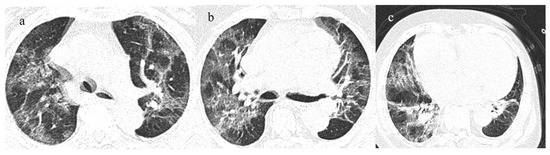

3.3.3. Pulmonary Fibrosis

- Kanne, J.P.; Little, B.P.; Schulte, J.J.; Haramati, A.; Haramati, L.B. Long-term Lung Abnormalities Associated with COVID-19 Pneumonia. Radiology 2023, 306, e221806. [Google Scholar] [CrossRef]

- Han, X.; Fan, Y.; Alwalid, O.; Zhang, X.; Jia, X.; Zheng, Y.; Shi, H. Fibrotic Interstitial Lung Abnormalities at 1-year Follow-up CT after Severe COVID-19. Radiology 2021, 301, E438–E440. [Google Scholar] [CrossRef]

- Watanabe, A.; So, M.; Iwagami, M.; Fukunaga, K.; Takagi, H.; Kabata, H.; Kuno, T. One-year follow-up CT findings in COVID-19 patients: A systematic review and meta-analysis. Respirology 2022, 27, 605–616. [Google Scholar] [CrossRef]

- Bocchino, M.; Lieto, R.; Romano, F.; Sica, G.; Bocchini, G.; Muto, E.; Capitelli, L.; Sequino, D.; Valente, T.; Fiorentino, G.; et al. Chest CT–based Assessment of 1-year Outcomes after Moderate COVID-19 Pneumonia. Radiology 2022, 305, 479–485. [Google Scholar] [CrossRef] [PubMed]

- Cocconcelli, E.; Bernardinello, N.; Giraudo, C.; Castelli, G.; Giorgino, A.; Leoni, D.; Petrarulo, S.; Ferrari, A.; Saetta, M.; Cattelan, A.; et al. Characteristics and Prognostic Factors of Pulmonary Fibrosis After COVID-19 Pneumonia. Front. Med. 2022, 8, 823600. [Google Scholar] [CrossRef] [PubMed]